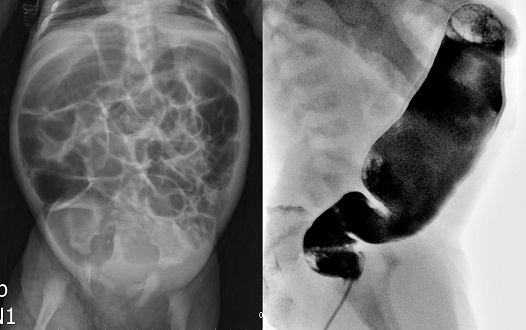

破題關鍵

嬰兒腹脹、長期便秘伴滲便,加上下消化道攝影顯示經典的「狹窄段-過渡區-擴張段」影像,高度提示先天性巨結腸症(Hirschsprung's disease)。解題核心是判斷哪項檢查或處置對於確診或治療前的管理幫助最小。

選項拆解